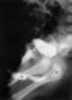

Male megalourethra

Distal urethral obstruction

Idiopathic megalourethra

Megacyst of the penis

Prune-belly syndrome